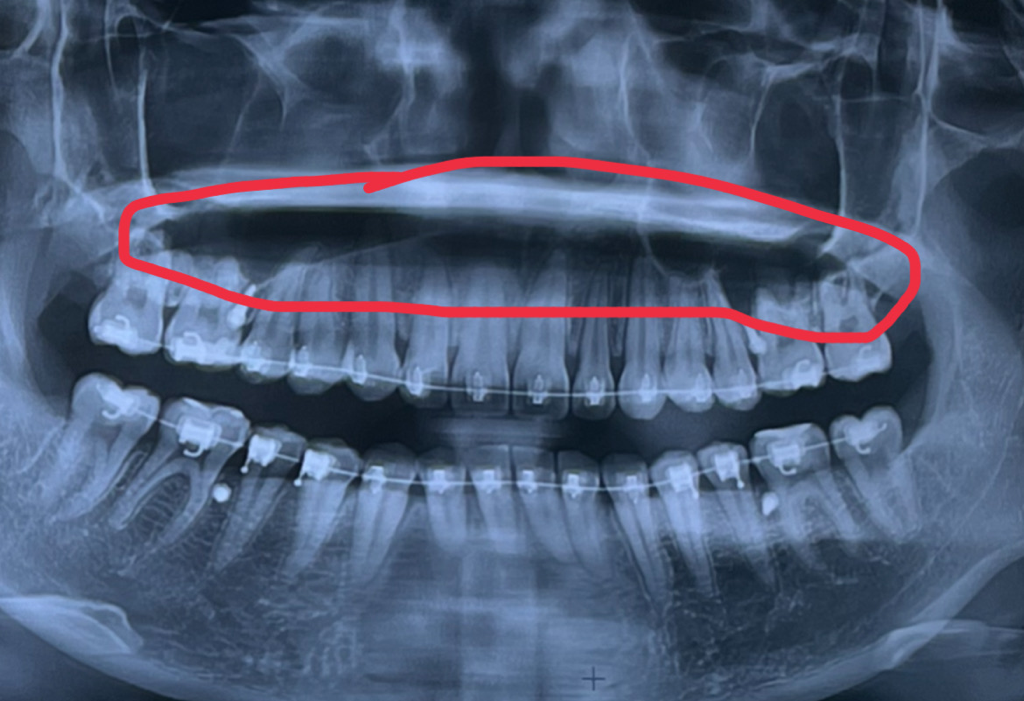

엑스레이상 보이는 이 부분은 뭔가요?? 이 부분이 예전보다 좀 길어진것같은데 뭘까요...

엑스레이를 찍으면 보이는 이 부분에 대해서 질문을 하고자합니다... 엑스레이를 찍으면 빈공간은 까맣게 보인다고 들었는데요, 제가 교정전에 찍은 사진과 타 치과에서 찍은 엑스레이를 비교해봤을때 저 부분이 좀 더 길어진것을 발견했는데 저 부분은 뭔가요? 그리고 저 부분이

길어질 수 있나요?

파노라마상 보이는 정상구조입니다. panorama soft tissue normal landmark 라고 구글에서 검색해보시면 다양한 관련 사진을 보실 수 있습니다. 위의 빈 공간은 혀, 연구개, 경구개(물렁 입천장, 단단입천장)이 왜곡되어 길게 보이는 것입니다.

해당 검은 빈 공간이 좀 더 길어진 것은 1. 비율상 그렇게 보일 수 있고 2. 교정 후 치아의 뿌리(치근)가 흡수되면서 상대적으로 그렇게 보일 수 있습니다.

엑스레이를 찍었을 때 실제로 비어서 까맣게 보이는 부위는 그 윗부분 코 옆의 양쪽으로 대칭적으로 있는 상악동이라는 공간입니다. 이건 위턱의 공기주머니라고 보시면 됩니다. 아마 이 부위를 빈 공간은 검게 나온다로 설명 들으신 것 같습니다.

해당부위는 상악의 구개부, 입천장입니다

사진을 찍는 높이에 따라서 나타나는 위치에 차이가 있어요